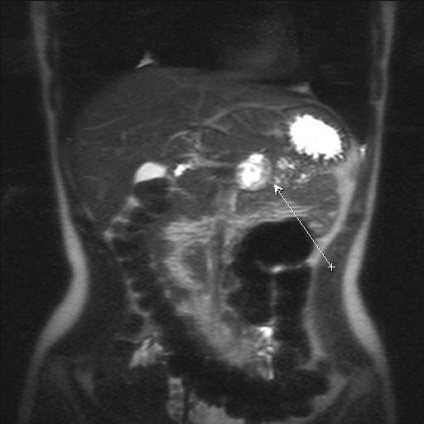

A képen - pseudotumor formájában krónikus pancreatitis